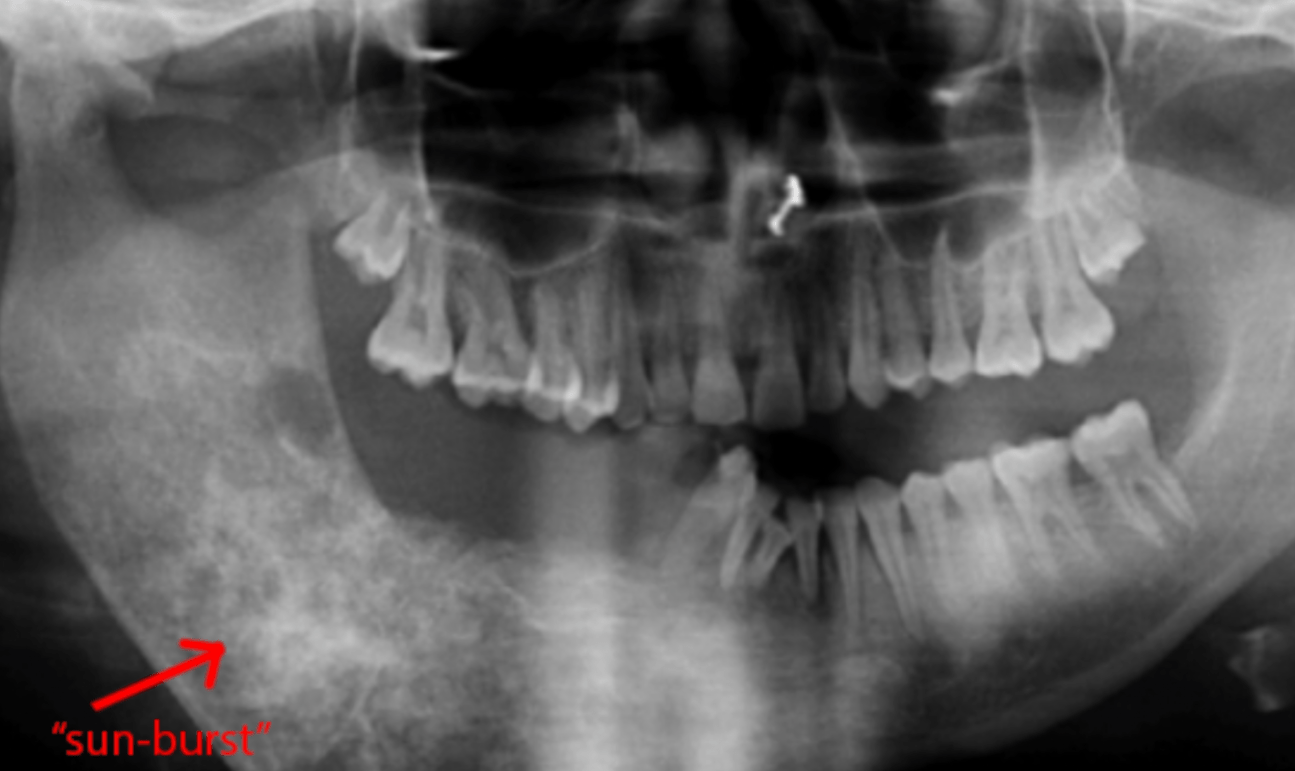

Radiological appearances if this neoplasm manifests as mixed radiopaque and radiolucent lesions with periodontal ligament widening. Lesions commonly include radiopaque, “starburst” proliferation of abnormal bone.

Osteosarcoma is a malignant bone neoplasm, most often characterized radiographically by radiopaque, “sunburst” lesions.